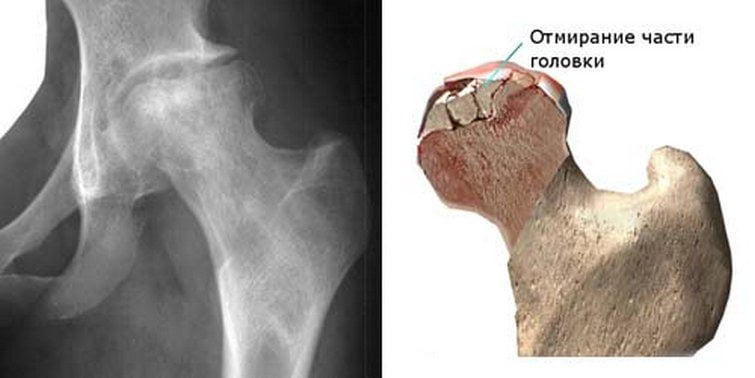

Асептический некроз головки бедренной кости: причины, симптомы, лечение

Асептический некроз головки тазобедренного сустава

Так называется дегенеративно-дистрофическая патология, для которой характерно повреждение отдельных участков костного мозга головки бедренной кости. Заболевание осложняется последующим развитием локального остеопороза и остеонекроза из-за расстройства кровообращения, дефицита питательных веществ в костных тканях.

Наиболее часто асептический некроз диагностируется преимущественно у мужчин 25-40 лет, при этом у 50% обследуемых выявляется поражение сразу двух бедренных костей. Толчком к развитию патологии становится расстройство локального кровообращения, что приводит к гибели отдельных участков костномозговых тканей и формированию отека в зоне некроза.

Процессы восстановления запускаются, но их недостаточно для репарации. Ей препятствуют парезы, спазм мелких кровеносных сосудов, застойные явления. Размеры омертвевшего участка неуклонно увеличиваются — патология распространяется на здоровые ткани.